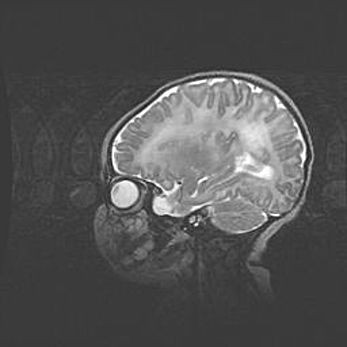

Подострая гематома правой гемисферы мозжечка.

Наружная гидроцефалия.

Возраст: 15 дней

Вес: 3100 г

Пол: женский

Окружность головы: 37 см

Срок гестации: 35-36 недель

При открытой наружной форме гидроцефалии у новорожденных расширяются и переполняются субарахноидные пространства.

Кровоизлияния в мозжечок имеют две клинико-анатомические формы: полушарные гематомы и кровоизлияния в червь.

К появлению этой патологии может привести: повреждения головного мозга, возникающие в результате асфиксии и гипоксии плода при беременности, или травмы во время родов. Редко гематома мозжечка может быть результатом первичной коагулопатии и сосудистой мальформации, диссеминированном внутрисосудистом свертывании, изоиммунной тромбоцитопении.